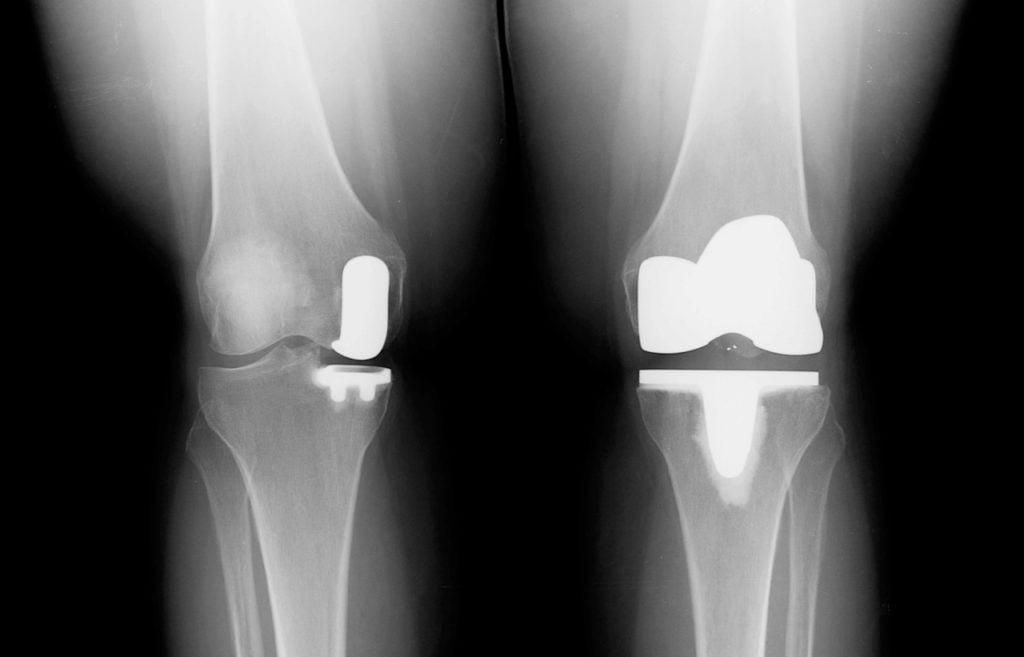

При полном эндопротезировании замене подлежат все три отсека, при частичном – только один из них. Большинство искусственных имплантатов состоят из четырех компонентов:

Частичное и полное эндопротезирование колена.